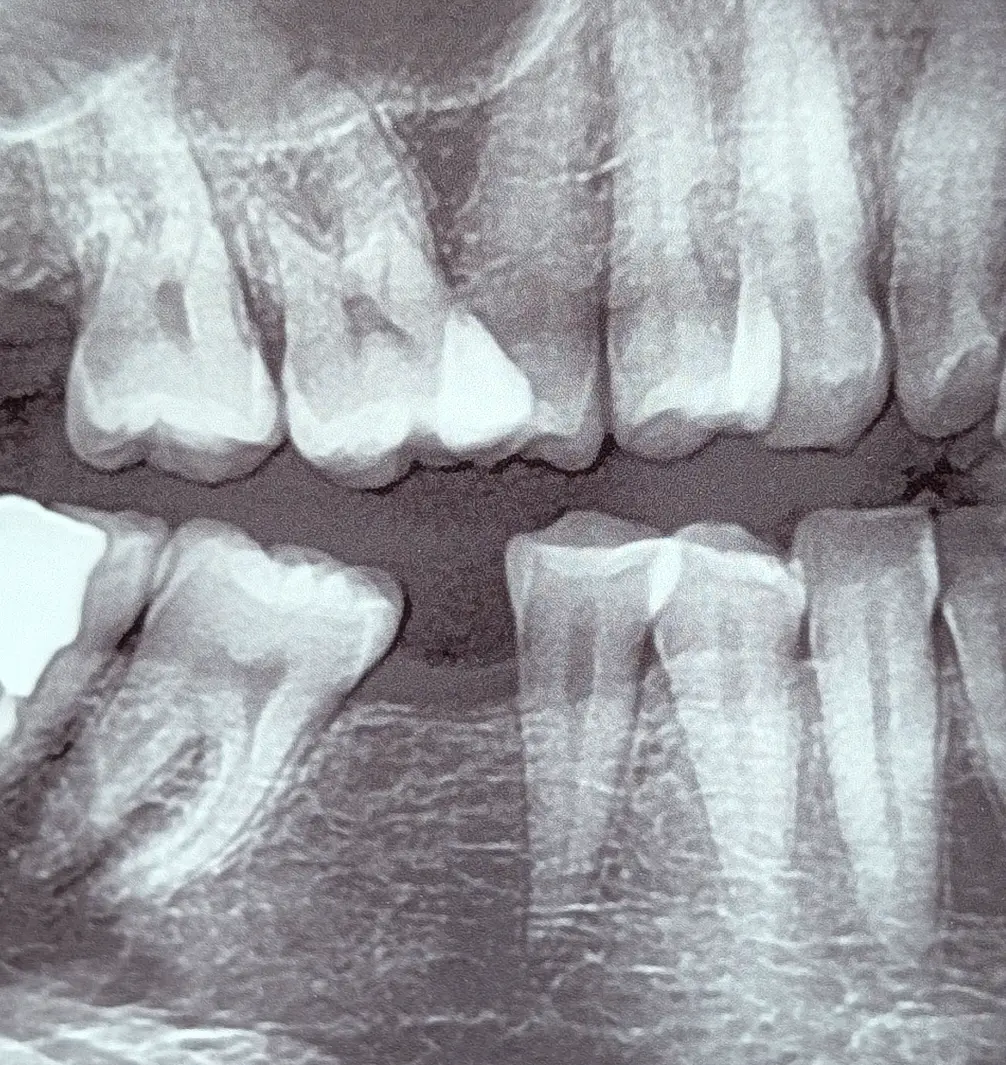

در معاینه، فضای بی‌دندانی قدیمی در ناحیه مولر مندیبل دیده می‌شد. سوپراایراپشن دندان مقابل بسیار خفیف بود و دندان‌های اطراف فقط تغییرات جزئی داشتند؛ در حدی که هیچ اثر معنی‌داری روی اکلوژن، فانکشن یا گیر غذایی ایجاد نکرده بود.

جایگزینی دندان، مسیر ساده‌ای نداشت. با توجه به وضعیت استخوان، احتمال نیاز به پیوند مطرح بود. و با وجود تیلت خفیف دندان خلفی، اگر بخواهیم بدون اصلاح وارد بازسازی شویم، ریسک گیر غذایی و طراحی‌های پرچالشِ پروتزی بالا می‌رود.